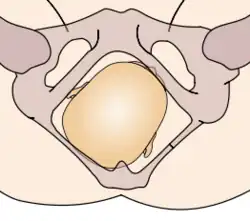

The vertex presentations are further classified according to the position of the occiput, both right, left, or transverse and anterior or posterior:

- Left Occipito-Anterior (LOA), Left Occipito-Posterior (LOP), Left Occipito-Transverse (LOT)

- Right Occipito-Anterior (ROA), Right Occipito-Posterior (ROP), Right Occipito-Transverse (ROT)

The occipito-anterior position is ideal for birth; it means that the baby is lined up so as to fit through the pelvis as easily as possible. The baby is head down, facing the spine, with their back anterior. In this position, the baby's chin is tucked onto their chest, so that the smallest part of their head will be applied to the cervix first. The position is usually "Left Occiput Anterior", or LOA. Occasionally, the baby may be "Right Occiput Anterior", or ROA.[5]